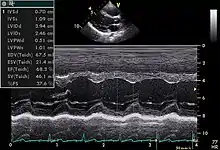

Echocardiogram in the parasternal long-axis view, showing a measurement of the heart's left ventricle